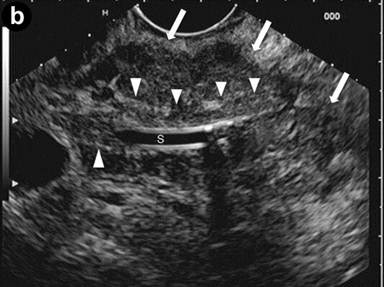

Patient#6: Diffuse form of autoimmune pancreatitis.

A 25-year-old man presented with jaundice, dilated bile ducts and an enlarged pancreatic gland at sonography; IgG4 levels were elevated (802 mg/dL). Endoscopic retrograde cholangiography (ERC) (Image 6a) showed stenosis of the distal common bile duct (arrows), and a stent was positioned. EUS linear scans (Image 6b) confirmed a substantially and diffusely enlarged pancreas, (arrows: pancreatic head), with echopoor echotexture and hyperechoic septa; the common bile duct, containing the stent, showed a three-layered, "sandwich-pattern" and thickening of the wall (arrowheads).